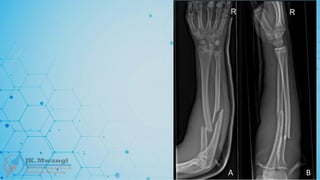

Galeazzi fracture

 A fracture of the radius with associated dislocation of the distal radioulnar joint

(DRUJ). Named after Ricardo Galeazzi, who described it in 1934

Monteggia fracture

 A fracture of the proximal third of the ulna with dislocation of the radial head.

Named after Giovanni Battista Monteggia in 1814